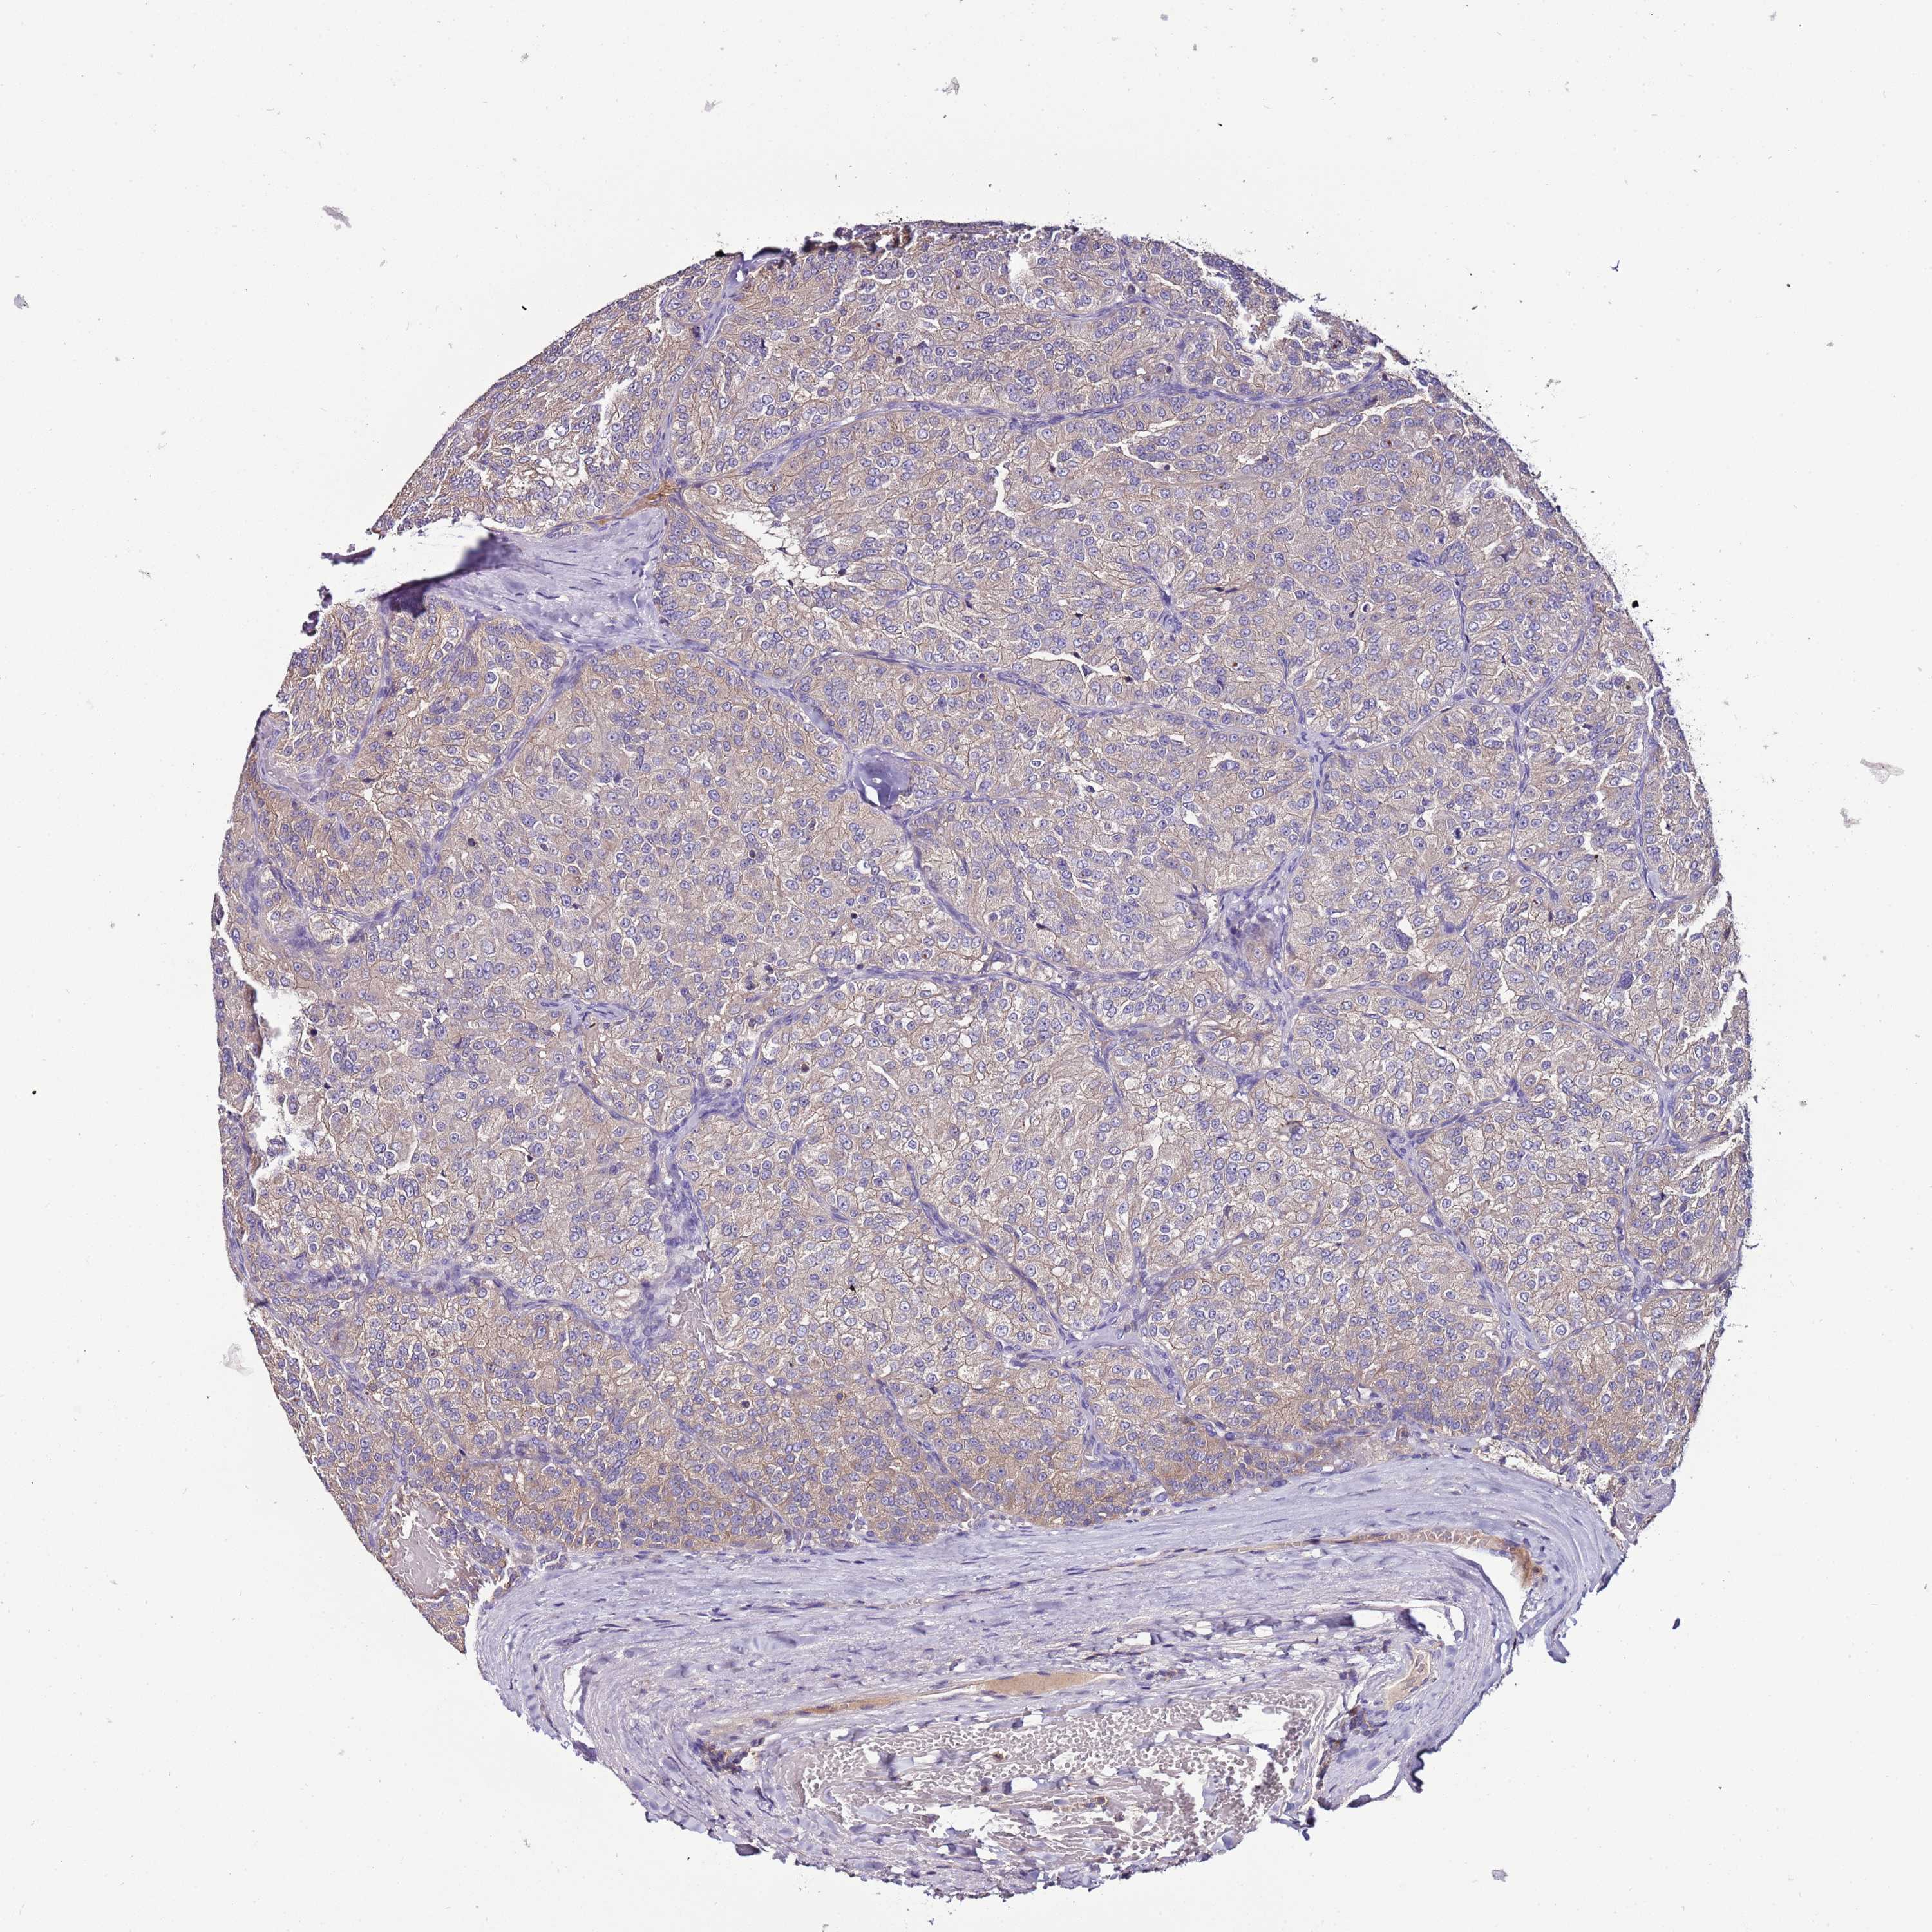

KIDNEY RENAL CLEAR CELL CARCINOMA (TCGA) - Interactive survival scatter ploti

The Survival Scatter plot shows the clinical status (i.e. dead or alive) for all individuals in the patient cohort, based on the same data that underlies the corresponding Kaplan-Meier plots. Patients that are alive at last time for follow-up are shown in blue and patients who have died during the study are shown in red.

The x-axis shows the expression levels (FPKM) of the investigated gene in the tumor tissue at the time of diagnosis. The y-axis shows the follow-up time after diagnosis (years). Both axes are complimented with kernel density curves demonstrating the data density over the axes. The top density plot shows the expression levels (FPKM) distribution among dead (red) and alive patients (blue). The right density plot shows the data density of the survived years of dead patients with high and low expression levels respectively, stratified using the cutoff indicated by the vertical dashed line through the Survival Scatter plot. This cutoff is automatically defined based on the FPKM cutoff that minimizes the p-score. The cutoff can be changed by dragging the vertical line or by entering a cutoff value in the square labeled "Current cut-off".

Under the Survival Scatter plot the p-score landscape (black curve; left axis) is shown together with dead median separation (red curve; right axis). Dead median separation is the difference in median mRNA expression between patients who have died with high and low expression, respectively. It is calculated as follows: median FPKM expression of dead patients with high expression - median FPKM expression of dead patients with low expression. This is intended to aid the user in visually exploring custom cutoffs and the associated p-scores and dead median separation.

Individual patient data is displayed and can be filtered by clicking on one or more of the category buttons on the top of the page. Categories describing expression level and patient information include: high, low, alive, dead, female, male and tumor stages. The scale of the x-axis can be toggled between linear and log-scale by clicking on the "x log" button. Mouse-over function shows TCGA ID, patient information and mRNA expression (FPKM) for each patient.

& Survival analysisi

Kaplan-Meier plots summarize results from analysis of correlation between mRNA expression level and patient survival. Patients were divided based on level of expression into one of the two groups "low" (under cut off) or "high" (over cut off). X-axis shows time for survival (years) and y-axis shows the probability of survival, where 1.0 corresponds to 100 percent.

IGIP is validated prognostic, high expression is favorable in Kidney Renal Clear Cell Carcinoma (TCGA)

: 9.85

Average pTPM 9.3

Number of samples 521